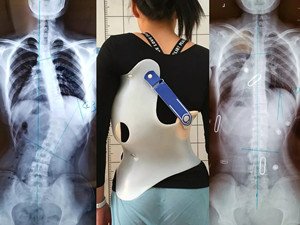

在青少年快速發(fā)育期內(nèi),身體長得越快,脊柱側(cè)彎的進展就越快。矯形支具通過長時的反向矯正力將脊柱維持在一個矯正的狀態(tài);然而由于長時間地佩戴支具會導(dǎo)致肌肉萎縮,當支具摘除,脊柱側(cè)彎回彈,且患者無法形成成自我矯正力,呼吸功能亦無法得到改善。最好是在穿戴支具的同時,配合體操訓(xùn)練,通過一系列矯正動作以及呼吸訓(xùn)練,平衡肌力,兩者結(jié)合不但可以穩(wěn)定脊柱,且能增加改善機會。